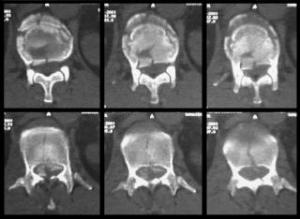

Corte Transversal

Dirfentes cortes trasversales de L1 demostrando la fragmentacion del cuerpo vertebral, con escaso compromiso del canal medular